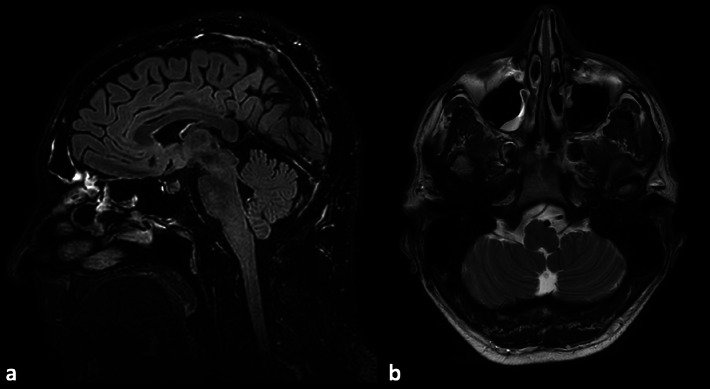

Neuroimaging in PRES: Isolated Brainstem and Spinal Cord Involvement Secondary to Aorto-Iliac Occlusive Disease-A Unique Case Report.

Teaching point: Consider atypical PRES and a vascular work-up in brainstem edema, especially in the setting of severe hypertension.